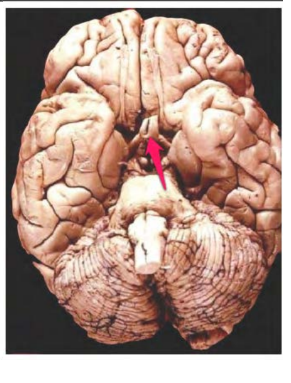

medulla oblongata

mesencephalon

tonsilla cerebelli sin.

pyramis sin. medullae oblongatae

corpus mamillare dex.

a. basilaris

pons

crus cerebri Dex.

corpus pineale

radix n. trigemini sin.

Vermis cerebelli

hemisphaerium dex. cerebelli

hypophysis